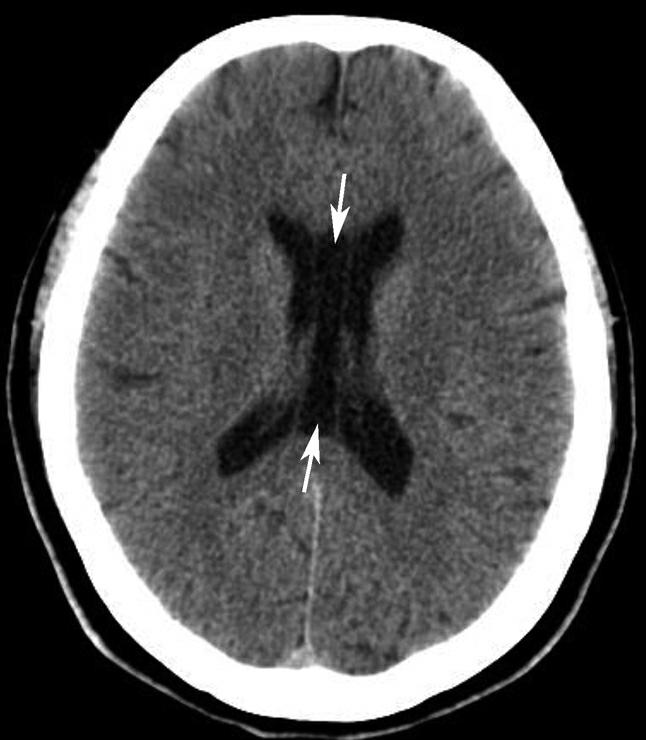

第三脑室正常成人前后径约12mm,左右宽约5mm,上下径也约为12mm。侧脑室后角两侧有时大小不等,右侧后角上下径约为38mm,左右径约为20mm;左侧后角上下径约为28mm,左右径约为15mm。测量双侧侧脑室前角间径与同平面脑横径的比值(R),正常平均值为30%。轻度扩大时为31%~39%,中度扩大为40%~46%,重度扩大时>47%。脑积水或脑萎缩等病理情况下脑室系统会扩大。不同年龄组正常脑室系统测量值存在差异,整体表现出测量值随着年龄增大而增大的趋势(图1-2-83、图1-2-84)。

图1-2-83 第三脑室测量

a线.第三脑室前后径;b线.第三脑室宽径

图1-2-84 侧脑室测量

R=双侧侧脑室前角间径(a)/同平面脑横径(b)